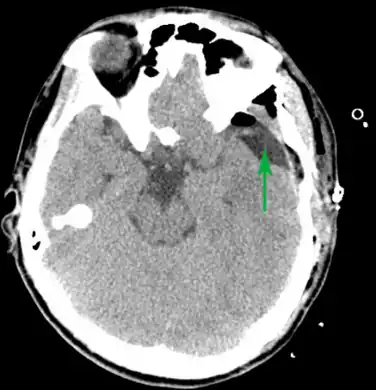

-

Male with complicated arachnoid cyst -

Arachnoid cyst as seen on a CT image of the brain -

Axial CT showing a typical arachnoid cyst left temporal